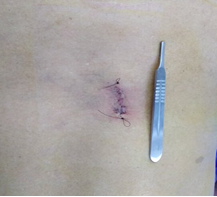

Las técnicas de mínima invasión ofrecen varias ventajas: incisiones pequeñas, menor riesgo de complicaciones, menor sangrado, menor agresión a los tejidos, rápida movilización y recuperación del paciente, generalmente el paciente puede ser dado de alta al día siguiente.